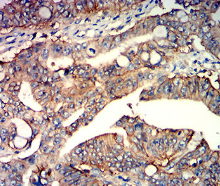

CD147 Mouse Monoclonal antibody[2D3A9]

BSG; OK; 5F7; TCSF; EMMPRIN

Immunogen:    Purified recombinant fragment of human CD147 (AA: extra 138-323) expressed in E. Coli.

IHC    1/200 - 1/1000